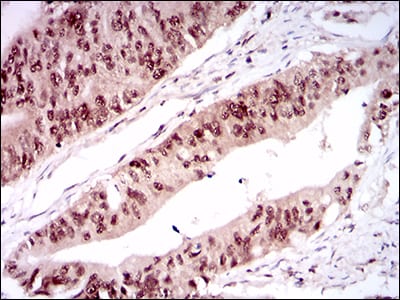

分类: 科研抗体货号: 30518别名: STSL应用: WB,IHC,FCM反应种属: Human

分类: 科研抗体货号: 30523别名:应用: WB,IHC,IF反应种属: Human

分类: 科研抗体货号: 30522别名: CD25; IL2R; TCGFR; IDDM10应用: WB,IHC,IF反应种属: Human,Mouse,Monkey,Rat